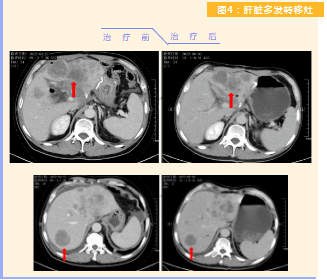

患者完成1周期治療后,上腹部疼痛癥狀基本消失,梗阻性黃疸癥狀緩解,腫瘤指標(biāo)下降(圖1),肺部多發(fā)轉(zhuǎn)移灶消失和縮?。▓D2),雙肺門(mén)淋巴結(jié)縮?。▓D3),肝臟多發(fā)轉(zhuǎn)移灶縮?。▓D4)。